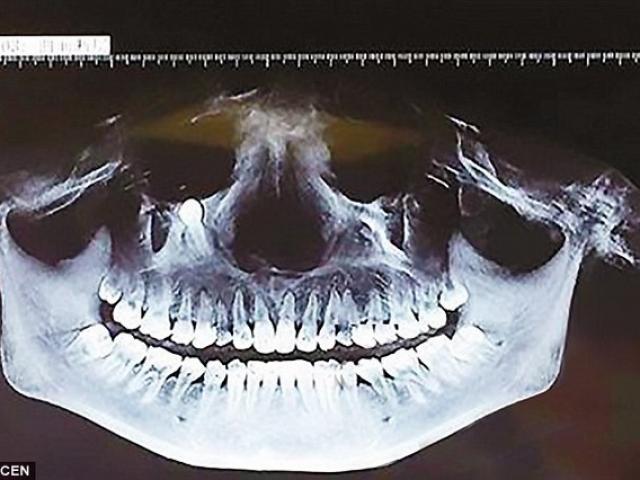

Con nhện trong tai nạn nhân.

Chồng của Lekshmi đưa vợ tới bệnh viện Colymbia Châu Á tại Hebbal, Ấn Độ. Tại đây, các bác sĩ đã vô cùng choáng váng khi thấy một con nhện sống chui ra từ trong tai người phụ nữ. Phải mất vài giờ đồng hồ, bác sĩ mới “lừa” và bắt được con nhện.

Bác sĩ Santosh Shivaswamy, người trực tiếp điều trị cho Lekshmi, nói: “Các ca bệnh có dị vật trong tai khá nhiều nhưng đây là lần hiếm hoi tôi thấy một con nhện chui ra từ tai người. Thủ thuật gắp con nhện ra gặp nhiều khó khăn do nó di chuyển liên tục”.

Phải mất vài giờ đồng hồ bác sĩ mới gắp được con nhện.